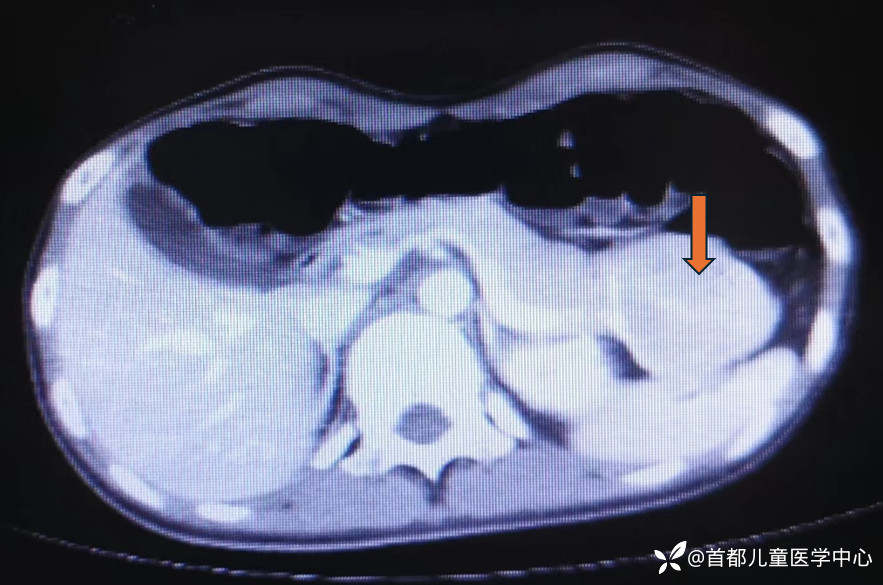

腹部CT:胰腺尾部、脾脏前方可见占位性病变,大小约4.4*5.6*6.7cm。

腹部核磁:胰腺尾部可见类圆形肿物影,呈T1W1低信号,T2WI稍高信号

腹部超声:左上腹近脾门处胰腺尾部可见一低回声包块,大小约6.7*4.1*4.8cm,内部回声强弱不等,未见钙化。